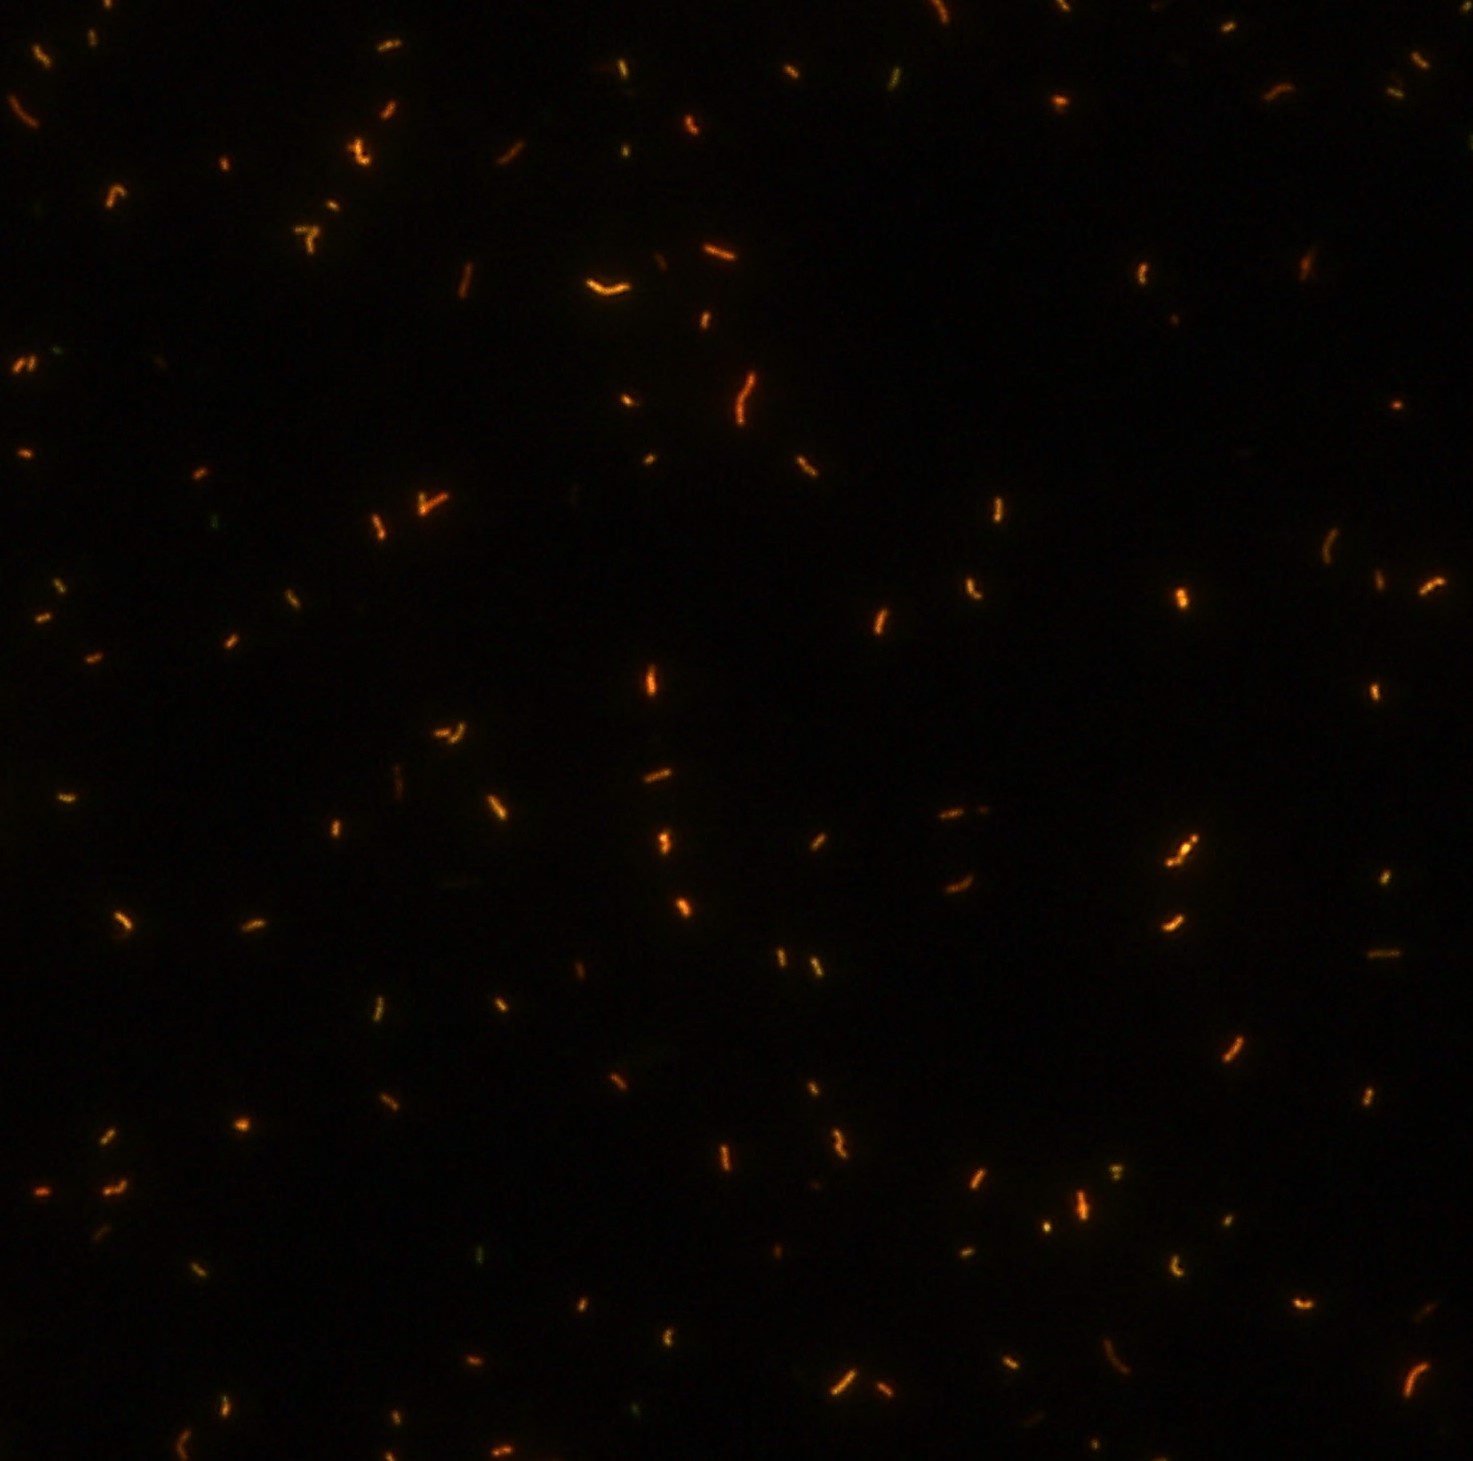

染色結(jié)果 (熒光法×400)

顯微染色技術(shù)是檢測結(jié)核桿菌方法之一。分枝桿菌細(xì)胞壁中含有分枝菌酸,其可以與染料牢固結(jié)合,具有“抗酸性”的特征。熒光染料金胺-羅丹明在染色中與抗酸生物細(xì)胞壁內(nèi)的分枝菌酸相結(jié)合,并耐受酸醇(脫色劑)清洗脫色。反染色劑高錳酸鉀被用來顯出染色生物。AFB(熒光)染色試劑盒設(shè)計既可用于自動染色機(jī),也可用于手工染色。產(chǎn)品穩(wěn)定性好,染色效果佳。

用于分枝桿菌、諾卡菌等細(xì)菌抗酸染色,包括熒光染色。